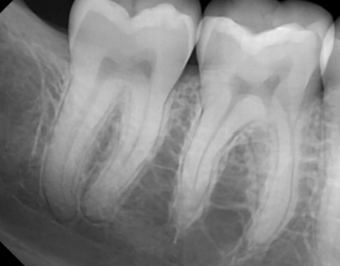

Describe this Radicular Cyst

Epicenter at apex (usually evidence of dental disease or trauma)

Well-defined, corticated

Lucent

Circular

Resorption, Displacement, Expansion (effect on adjacent structures)

Why is this Radicular cyst less circular/oval in this case?